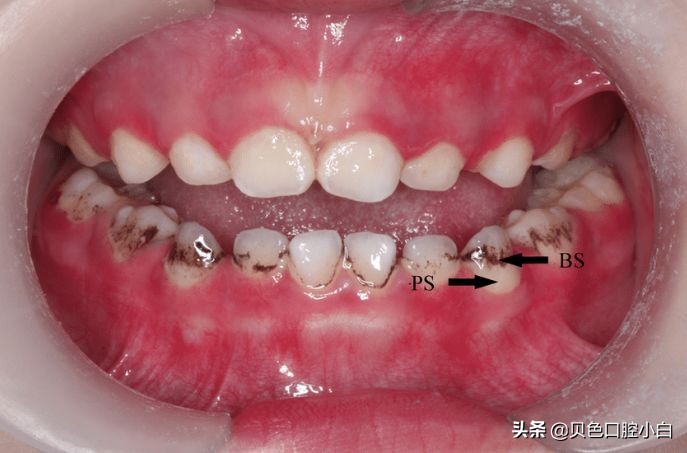

牙面色素沉着是一种外源性着色(black stain,简称BS)。

这个黑色沉积是一种牙齿外在的颜色改变,与牙龈边缘平行分布或表现为不连续的黑点,儿童牙齿外源性黑色素沉着常常发生在牙齿靠近牙龈边缘外。既可以影响乳牙也可以影响恒牙。不好看,但对功能影响不大。